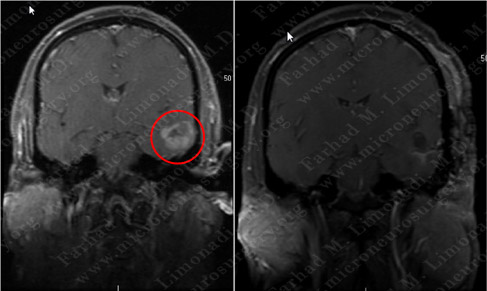

Post-op Imaging

Before Operation After Operation

Post-op MRI shows radiographic resection of the tumor.